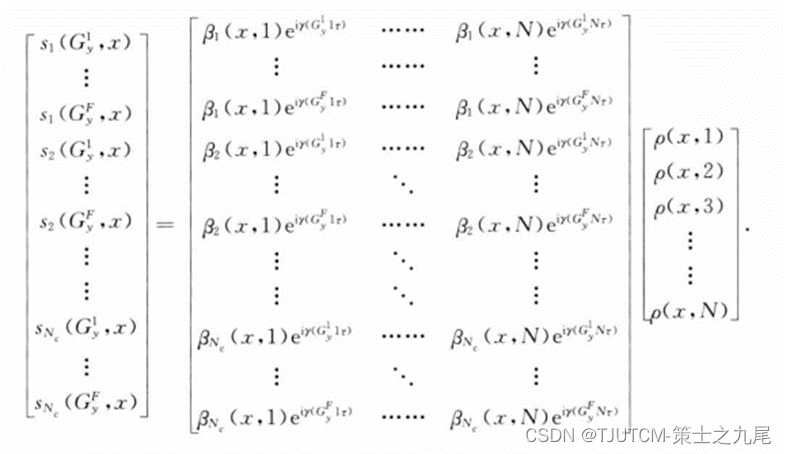

SPACE RIP算法把pMRI重建表示成一个矩阵求逆问题。这个算法要求很大的矩阵求逆,因此有 很长的重建时间。其优点是灵活度高,任何K空间轨迹都适用,线圈排列也可以是任意的。

图像中的各列是分别重建的。假若图像有N行M列,则矩阵方程中x应取1-M个离散值,对应有M个这样的方程。要重建M列图像,需要对M个灵敏度相位编码矩阵求逆。这里的矩阵不必是方阵,对每一列必须计算其广义逆矩阵。相位编码步数F的选择影响重建质量。增大F导致矩阵的秩增大,产生的广义逆矩阵的条件数好,噪声放大的程度低,信噪比高,但代价是 重建计算量增大。

左边的项是有Nc* F个元素的矢量,对于所有Nc个线圈,包含F个相位编码值;最右边的项是代表一列元素的像的N元矢量;中间项是一个有Nc*F行和N列的矩阵,是基于灵敏度轮廓和所用的相位编码构成的。

对于沿x轴各个位置解方程产生图像诸列的重建。